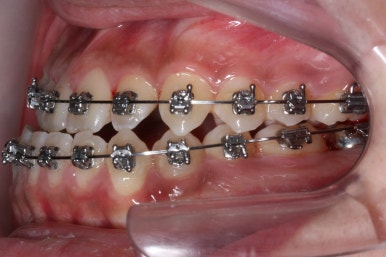

위 사진들은 부산주걱턱교정 키다리아저씨치과에 내원하셨을 당시의 입안 모습입니다.

입 안의 모습에서도 주걱턱의 특징으로는

하악이 앞으로 나와있습니다.

윗니는 뻐드러지고 아래 앞니는 뒤쪽으로 쓰러져 있습니다.

교합이 맞지 않습니다.